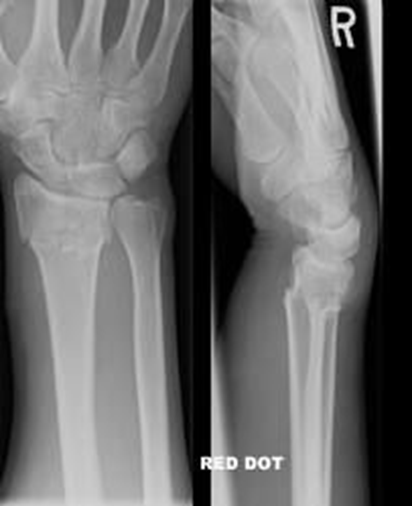

(2)Colles 骨折

Colles 骨折即伸直型桡骨远端骨折,1814 年 Abraham Colles 首先详细描述此类骨折,故命名为 Colles 骨折,是人体最常见的骨折之一,占所有骨折的 10% ,多见于老年人。